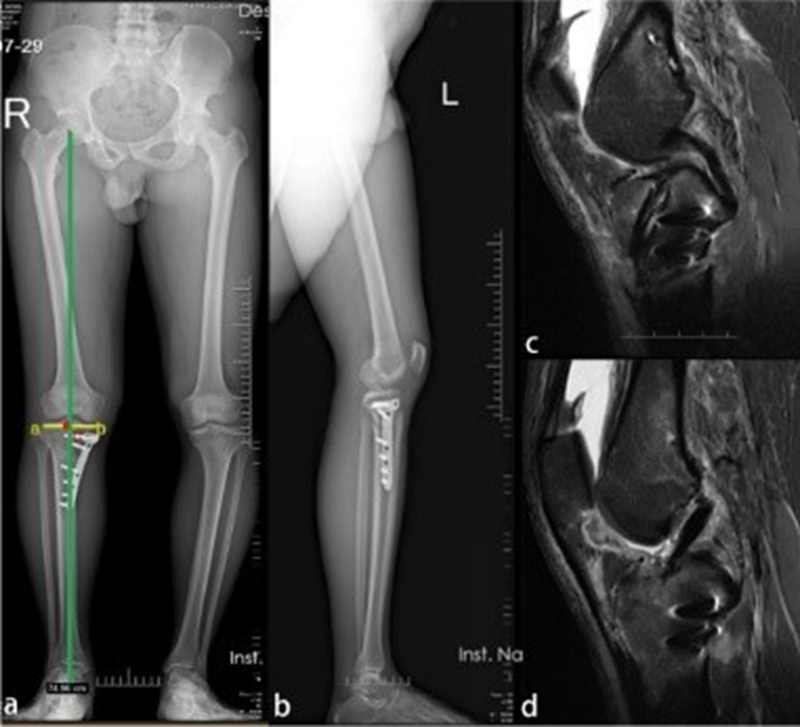

图4

Deng等人报道一例ACLR联合OWHTO治疗膝内翻合并ACL撕裂的病例。一名27岁男性因运动损伤入院,诊断为与内翻畸形和胫骨后倾过大相关的ACL撕裂。之后,该患者接受了ACLR联合OWHTO以纠正内翻畸形和过大的胫骨后倾角[7]。